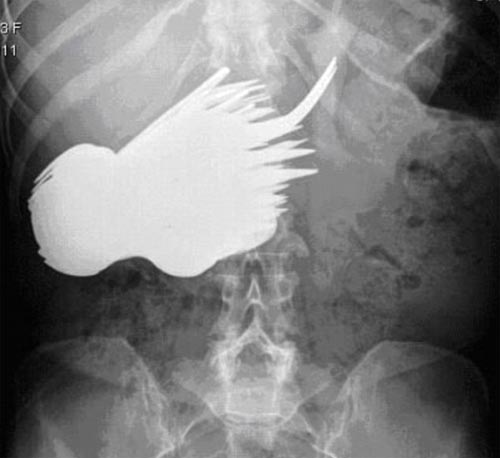

中新网10月29日电 据英国媒体报道,英国一名52岁的妇女日前因为肚子疼到医院就诊,医生为她照X光透视,却被吓得目瞪口呆,原来她的肚子内竟藏有78件餐具!

据报道,医生迅速为她实施了手术,将这些叉子、勺子一一取出。医生表示,这名妇女可能患上了一种强迫症,每次当她坐在餐桌前,就会毫不自主的吃掉餐具,却对一桌食物不感兴趣。